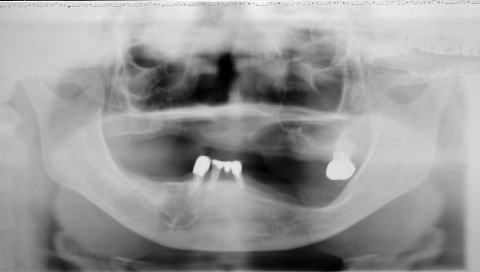

(図4)32年経過(2007年3月5日)、70歳。十分機能している